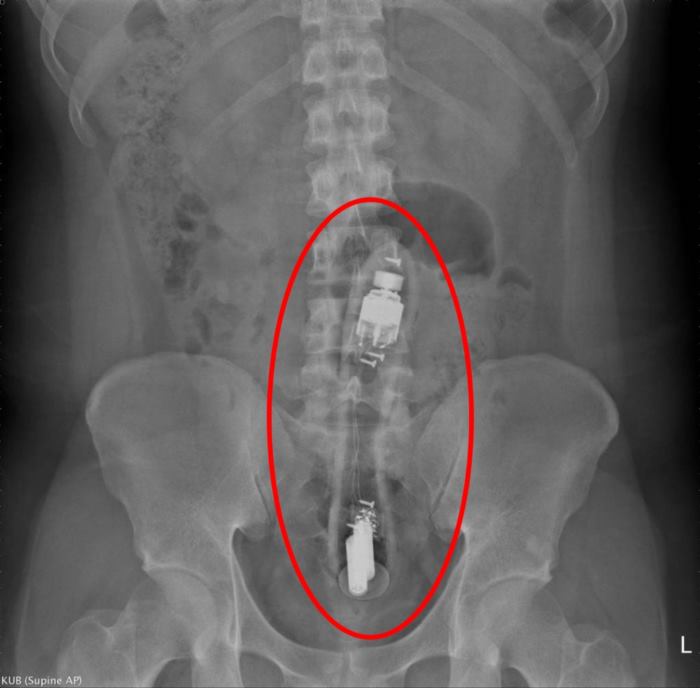

ในขณะที่เขาพยายามดึงมันออกตลอดทั้งคืน แต่ก็ทำไม่สำเร็จ ดร. เฉิน เริ่มจากการคลำตรวจในเบื้องต้น จนสามารถยืนยันได้ว่า มี "วัตถุแข็ง" บางอย่าง อยู่ในทวารหนักของคนไข้ชายรายนี้จริง จากนั้นจึงได้ทำการเอกซเรย์เพื่อตรวจเพิ่ม ก่อนที่ผลจะปรากฏออกมาว่า วัตถุดังกล่าวนั้นมีขนาดยาวประมาณ 15-20 เซนติเมตร อยู่ในทวารหนักจนไปติดกับลำไส้ใหญ่ส่วนคด (Sigmoid Colon)

ภาพจาก 陳致一醫師